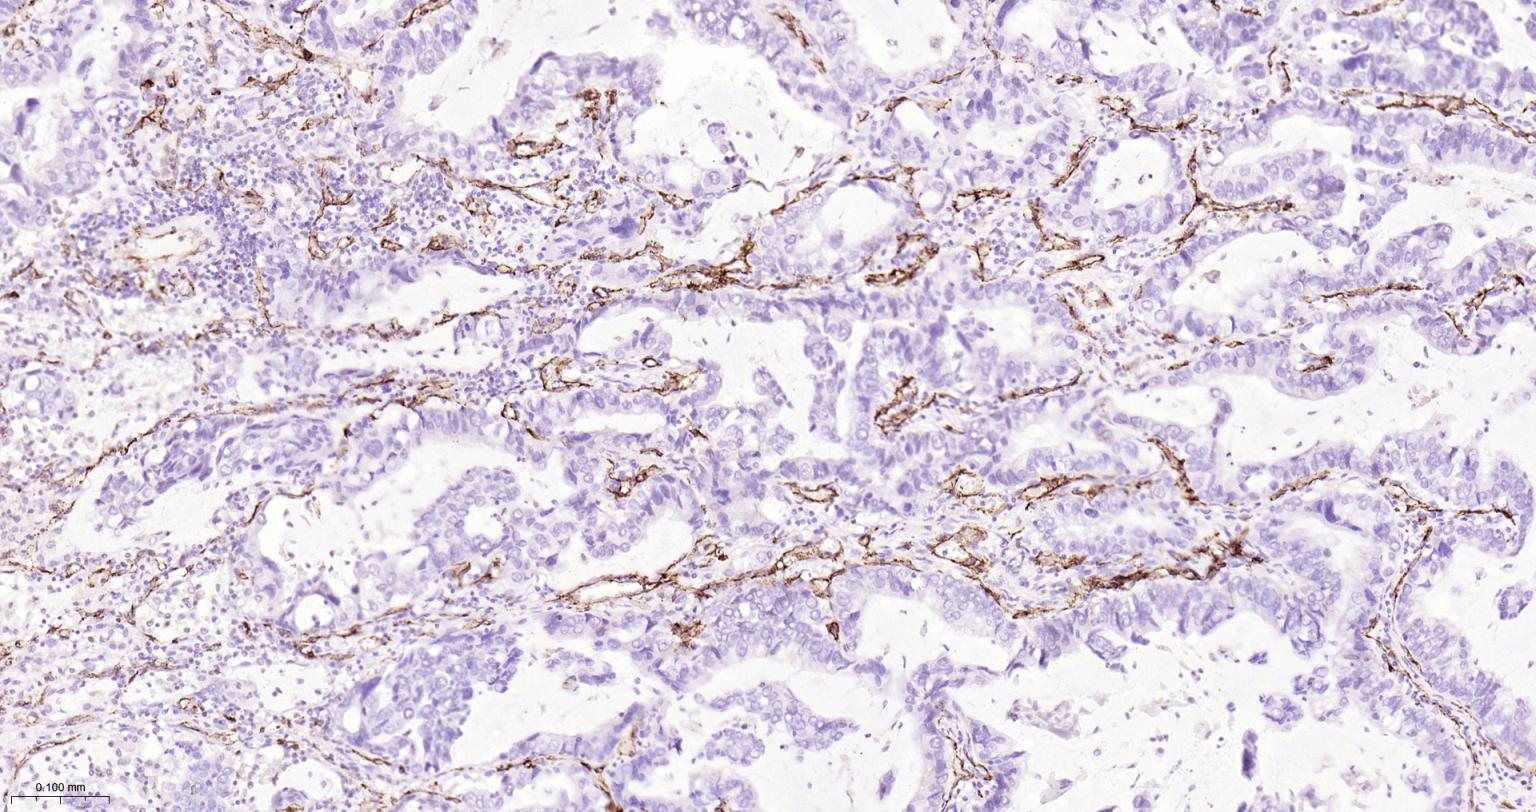

| IHC-P | Human | 1:200-2000 | |

Expressed on platelets and leukocytes and is primarily concentrated at the borders between endothelial cells (PubMed:18388311, PubMed:21464369).

Cell adhesion molecule which is required for leukocyte transendothelial migration (TEM) under most inflammatory conditions (PubMed:19342684, PubMed:17580308).